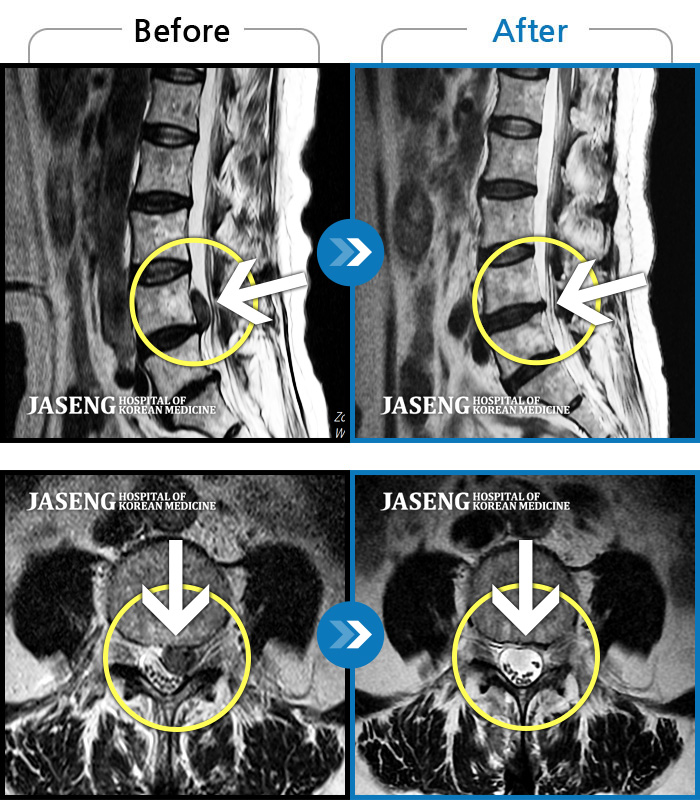

MRI 치료사례

허리 골반이 욱신욱신하게 아프고 허리 숙일 때 다리가 당겼다.